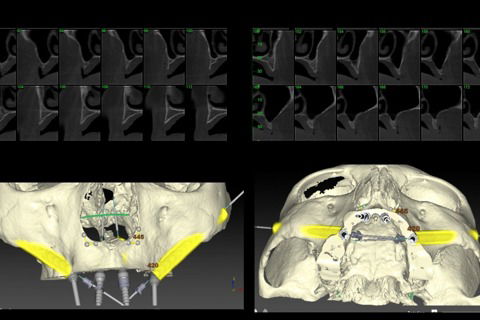

Avaliação dos exames tomográficos, planejamento e cirurgia virtual

Foto 04 Avaliação dos exames tomográficos, planejamento e cirurgia virtual